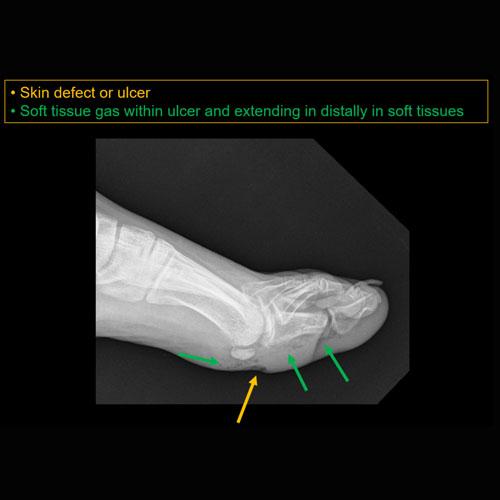

Section 1 Submit Findings CB1119 Findings Findings There are limitations. Yes No There is soft tissue reticulation, fullness, or obscuration of normal fat planes. Yes No There is soft tissue ulceration. Yes No There is soft tissue gas. Yes No There is a foreign body. Yes No There are fractures. Yes No There is periosteal reaction or osseous destruction suggesting osteomyelitis. Yes No There is cloaca, sequestrum, or involucrum. Yes No There is a joint effusion. Yes No There is periarticular osteopenia or erosions to suggest septic arthritis. Yes No There is malalignment, degenerative changes, or other gross internal derangement of the visualized joints. Yes No